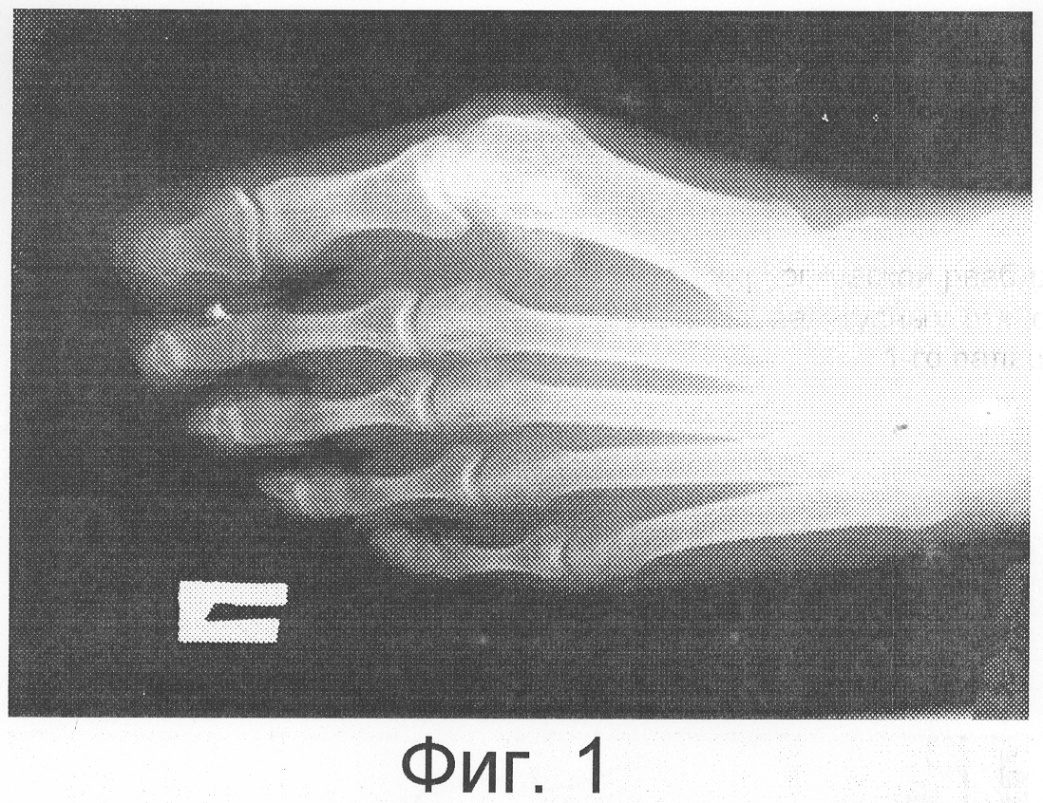

Пример. Больная К., 26 лет. Диагноз «Hallux valgus обеих стоп, более выраженный справа». На Фиг.1 представлена рентгенограмма правой стопы в прямой проекции до операции.